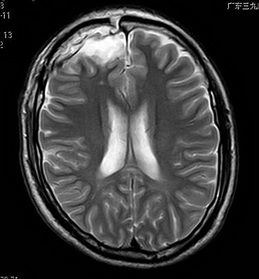

经吴杰主任及其团队详细术前评估后,钟先生接受了右侧额叶癫痫灶切除术,术后至今没有出现癫痫发作。术后病理示:脑软化灶。

术后MR